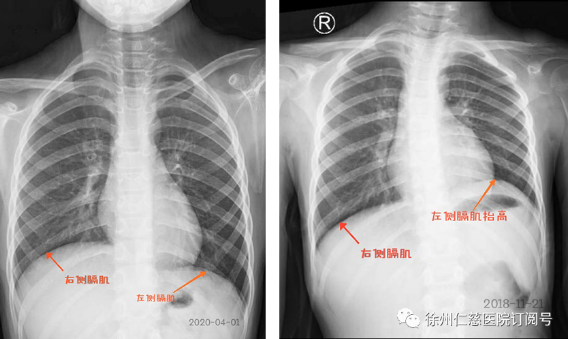

2020年4月,伤后一年半,甜甜的肩关节外展、肘关节屈曲都比之前有力了,肩肘活动度均已接近正常水平,拍胸片显示,左侧膈肌降下来了,说明膈神经也已经恢复。甜甜的妈妈特别高兴,十分感激陈主任的救治,她说不但自己担心孩子恢复得不好,甜甜也经常小声地问她:“妈妈,我什么时候才能好啊?”陈主任感慨道:“小姑娘很勇敢,比成年人所承受的疼痛和辛苦更多,现在神经恢复了,她的心结也打开了!”一年多以来闷闷不乐的甜甜终于露出了灿烂的笑容。

胸部平片

肩外展功能(左图) 屈肘功能(右图)